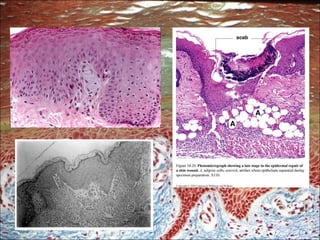

El documento resume los componentes principales del sistema tegumentario, incluyendo la epidermis, dermis, células de la epidermis, inervación sensitiva y anexos cutáneos. La epidermis está compuesta por cinco estratos, mientras que la dermis contiene la dermis papilar y reticular. Las células de la epidermis incluyen queratinocitos, melanocitos, células de Langerhans y células de Merkel. Los anexos cutáneos son folículos pilosos, glándulas sebáceas y sud